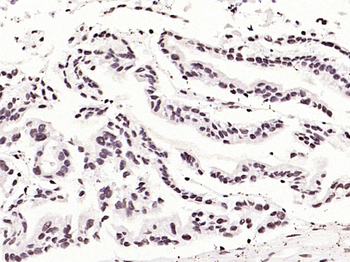

50 μl, 100 μl - KLF4 Recombinant Rabbit Monoclonal Antibody [orb608075]Featured

FC, ICC, IF, IHC-Fr, IHC-P, WB

Human, Mouse, Rat

Rat

Rabbit

Recombinant

Unconjugated

200 μl, 50 μl, 100 μl - Featured